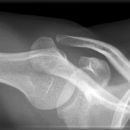

Schulter axial

Schulter axial liegend (caudo-cranial):

Patient in Rückenlage, möglichst weit an Tischkante, Körperachse parallel zum Tisch, Arm in Schultergelenk rechtwinklig abduzieren und unterpolstern, so dass das Schultergelenk in Kassettenmitte kommt, Kassette senkrecht zum Tisch, hinter die Schulter möglichst weit an den Hals geschoben, Kopf zur gesunden Seite drehen.

Schulter axial sitzend:

1. Möglichkeit: Patient sitzt auf dem Stuhl, Arm möglichst weit abduziert, Kassette unter die Axilla bzw. den Oberarm weit auf die auf dem Buckytisch gelagerte Kassette gezogen, Kopf immer zur Gegenseite drehen.

2. Möglichkeit: Patient sitzt auf dem Stuhl, Arm möglichst weit abgespreizt, Kassette auf der Schulter, evtl. mit 15° Keil unterpolstern, Kassette dem Patienten bis an den Hals schieben.

Röhre 90° caudo-cranial, zielt auf Humeruskopf (Axilla) fast parallel zur Körperachse auf das letzte Drittel der Kassette.

bei 1. senkrecht oder 15-20° ellenbogenwärts auf die Schultermitte und Kassette.

Bei 2. von unten in die Axilla senkrecht auf das letzte Drittel der Kassette.

Freier Durchblick durch Humeroglenoidalgelenk, unverzerrte Darstellung von Proc. Coracoideus und AC-Gelenk, das sich in den Oberarmkopf projiziert.